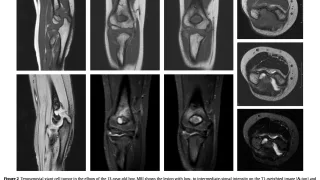

手術日+575日目 2025/9/25(木)(びまん型腱滑膜巨細胞腫)

午前の病院での仕事とびまん型腱滑膜巨細胞腫の患者体内時計が少しずれているのか, 今朝は5時過ぎに目が覚めました.起きるか, もう一度眠るか迷いましたが, 結局寝直して7時に起床.カーテンの隙間から差し込む朝日が, 穏やかな一日の始まりを告げ...